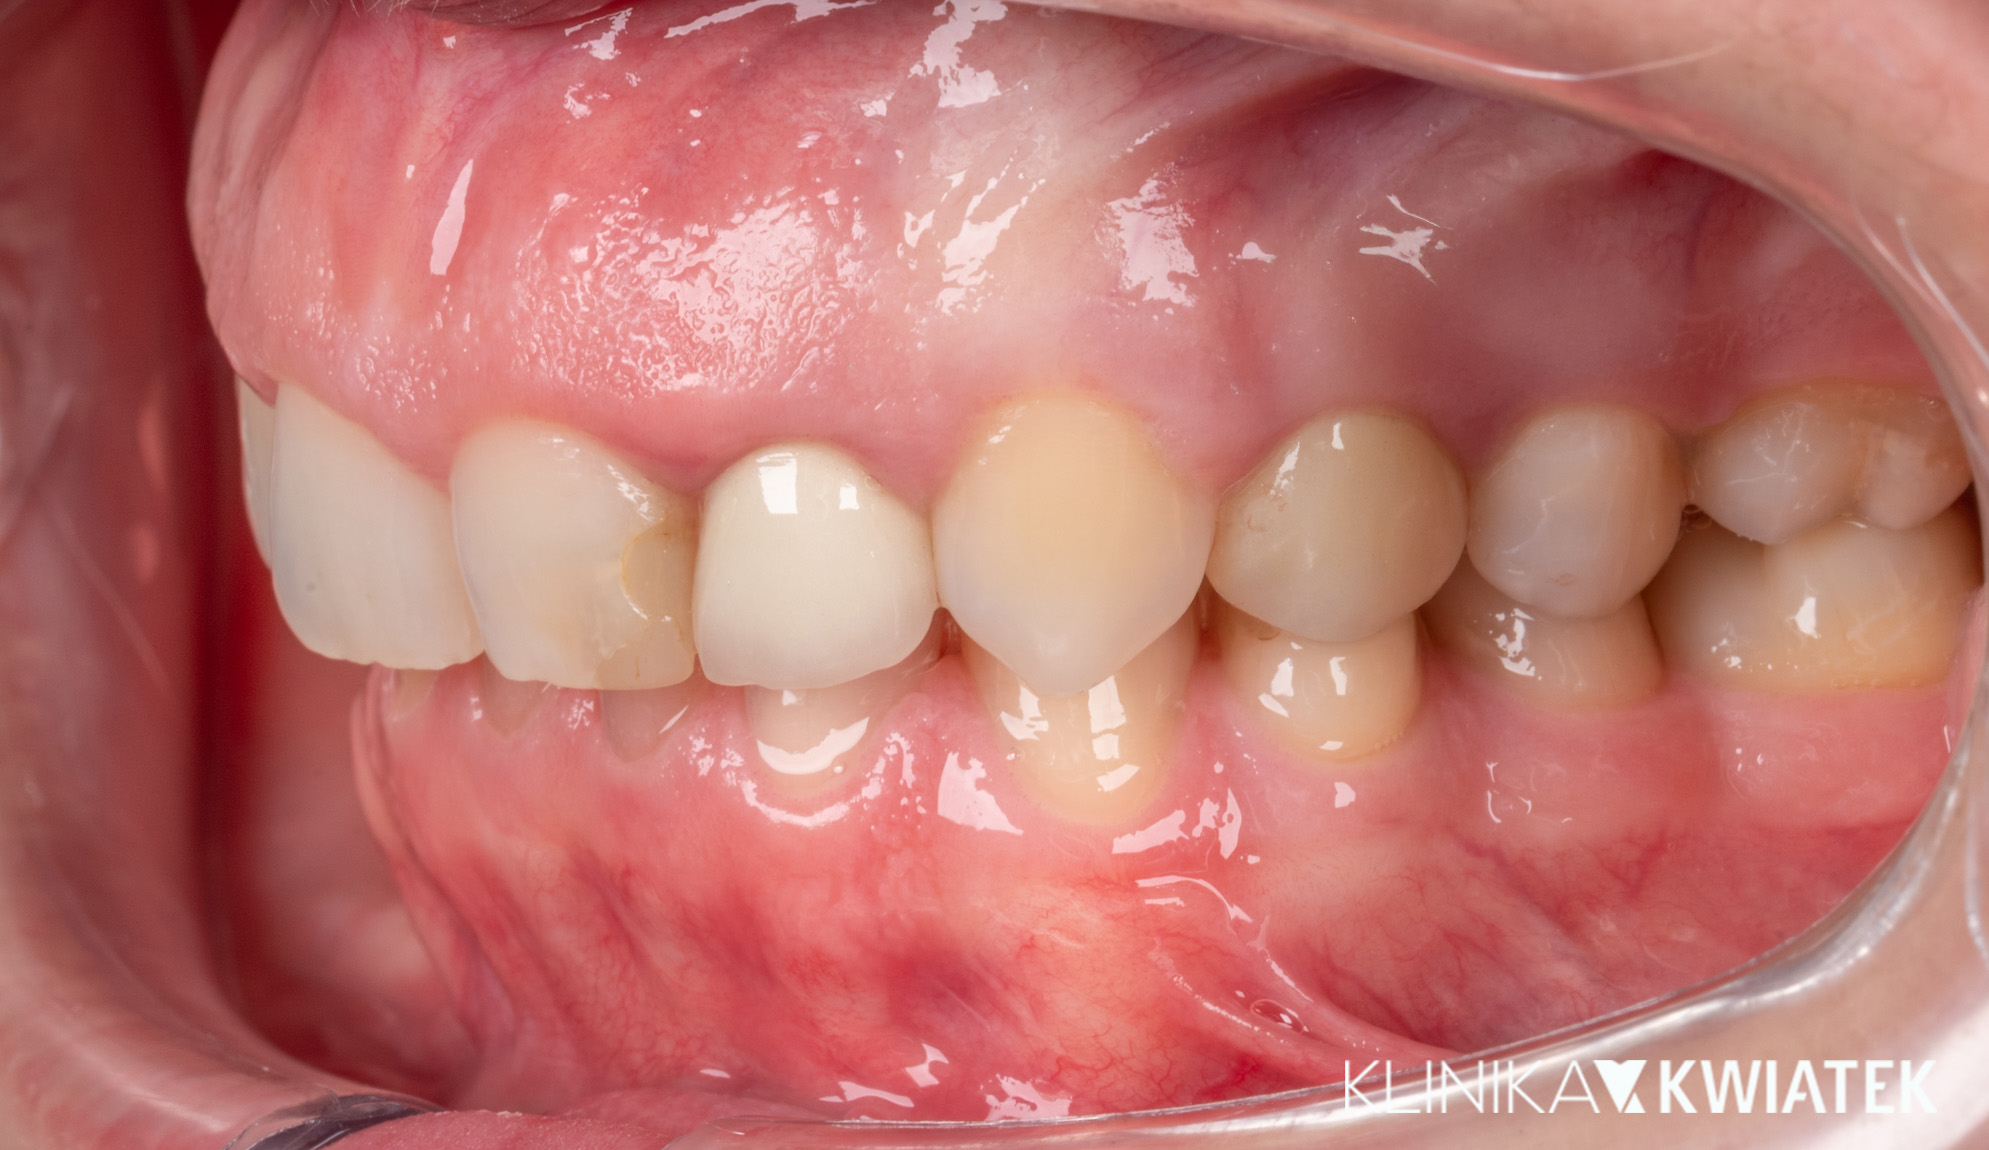

PRZED

PO